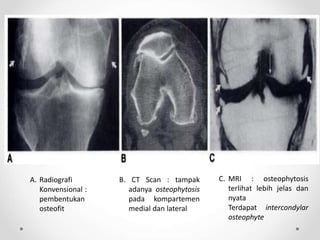

A. Radiografi

Konvensional :

pembentukan

osteofit

B. CT Scan : tampak

adanya osteophytosis

pada kompartemen

medial dan lateral

C. MRI : osteophytosis

terlihat lebih jelas dan

nyata

Terdapat intercondylar

osteophyte

A. Radiografi Konvensional : pembentukan osteofit B.CT Scan : tampak adanya osteophytosis pada kompartemen medial dan lateral C. MRI : osteophytosis terlihat lebih jelas dan nyata Terdapat intercondylar osteophyte